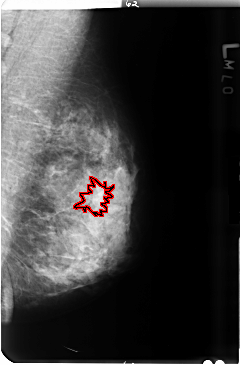

B_3495_1.LEFT_MLO

LEFT_MLO LINES 4736 PIXELS_PER_LINE 3120 BITS_PER_PIXEL 12 RESOLUTION 50 OVERLAY

FILE: B_3495_1.LEFT_MLO.OVERLAY

TOTAL_ABNORMALITIES 1

ABNORMALITY 1

LESION_TYPE CALCIFICATION TYPE PUNCTATE DISTRIBUTION SEGMENTAL

LESION_TYPE MASS SHAPE ARCHITECTURAL_DISTORTION MARGINS ILL_DEFINED

ASSESSMENT 2

SUBTLETY 1

PATHOLOGY BENIGN

TOTAL_OUTLINES 1

BOUNDARY